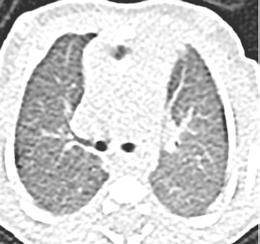

Debido al empeoramiento clínico se solicitó una ecografía de abdomen durante la cual estuvo presente el equipo tratante y en la que se evidenció aumento del líquido libre de aspecto ecogénico sin otras alteraciones. Sin embargo, ante la evolución tórpida y la localización de la contusión abdo minal se comunicó al radiólogo la posibilidad de una perforación intestinal, quien realizó una segunda exploración ecográfica enfocada en las zonas cefálicas y anteriores del abdomen en las que se ubicaría el aire, entonces se visualizaron artefactos en la superficie hepática que sugerían burbujas aéreasextraluminales (Figura 2A). Se realizó una radiografía toracoabdomi nal (RxTA) que confirmó la presencia de neumoperitoneo subdiafragmático bilateral (Figura 2B).

Figura 2. Ecografía con burbujas aéreas extraluminales en la superficie hepática sugestivas de neumoperitoneo (A, flechas). RxTA con neumoperitoneo subdiafragmático bilateral (B, flechas).